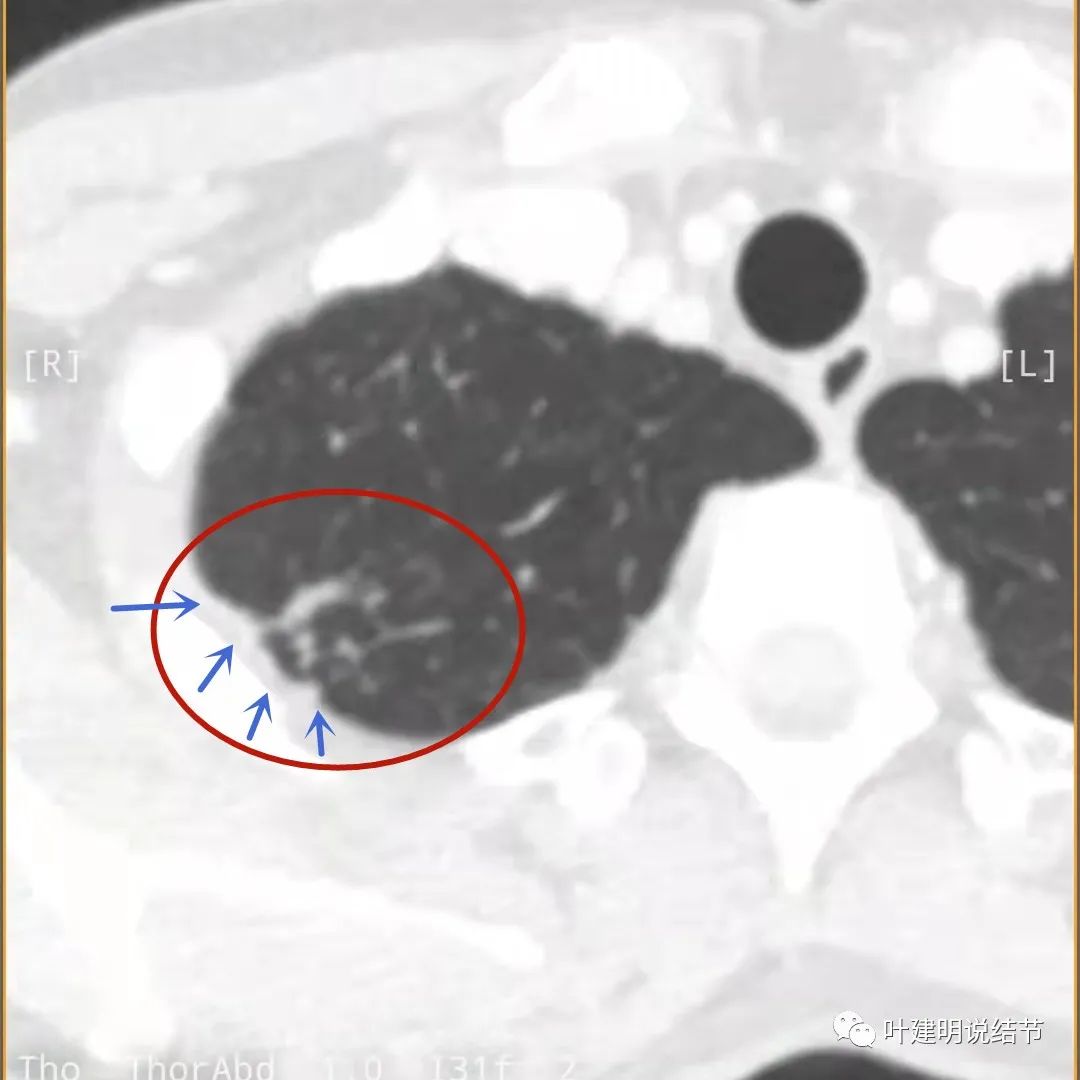

我们再来看薄层的CT图像:

病灶出现,模糊的磨玻璃影

部分密度过高,且呈条状

邻近胸膜有增厚(蓝色箭头),主病灶边界较清(红色箭头),实性部分密度过高(粉色箭头),旁边有磨玻璃影,散且模糊(砖色箭头)

邻近胸膜有增厚(蓝色箭头),主病灶实性部分密度过高(粉色箭头),旁边有磨玻璃影,散且模糊(砖色箭头)

邻近胸膜有增厚(蓝色箭头),主病灶实性部分密度过高(粉色箭头),旁边有磨玻璃影,散且模糊(砖色箭头),病灶有空腔(黄色箭头)

主病灶边界较清(红色箭头),实性部分密度过高(粉色箭头),病灶边缘向内凹,缺乏膨胀性(桔色箭头),病灶有空腔(黄色箭头)